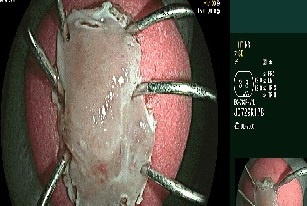

Ê-kíp mổ thuộc các bác sĩ khoa Ung bướu phối hợp cùng khoa Gây mê hồi sức thực hiện. Qua đường rạch nhỏ ở ổ bụng, phẫu thuật viên thắt các mạch máu trung tâm, sau đó dùng dụng cụ nội soi cắt bỏ đoạn đại tràng sigma có khối u dưới sự hỗ trợ của hệ thống nội soi 3D hiện đại. Tiếp đó, các bác sĩ nạo vét hạch xung quanh và khâu nối lại ruột để tái lập đường tiêu hóa.

ung thu da day anh 1

Bác sĩ thăm khám cho bệnh nhân sau ca phẫu thuật.